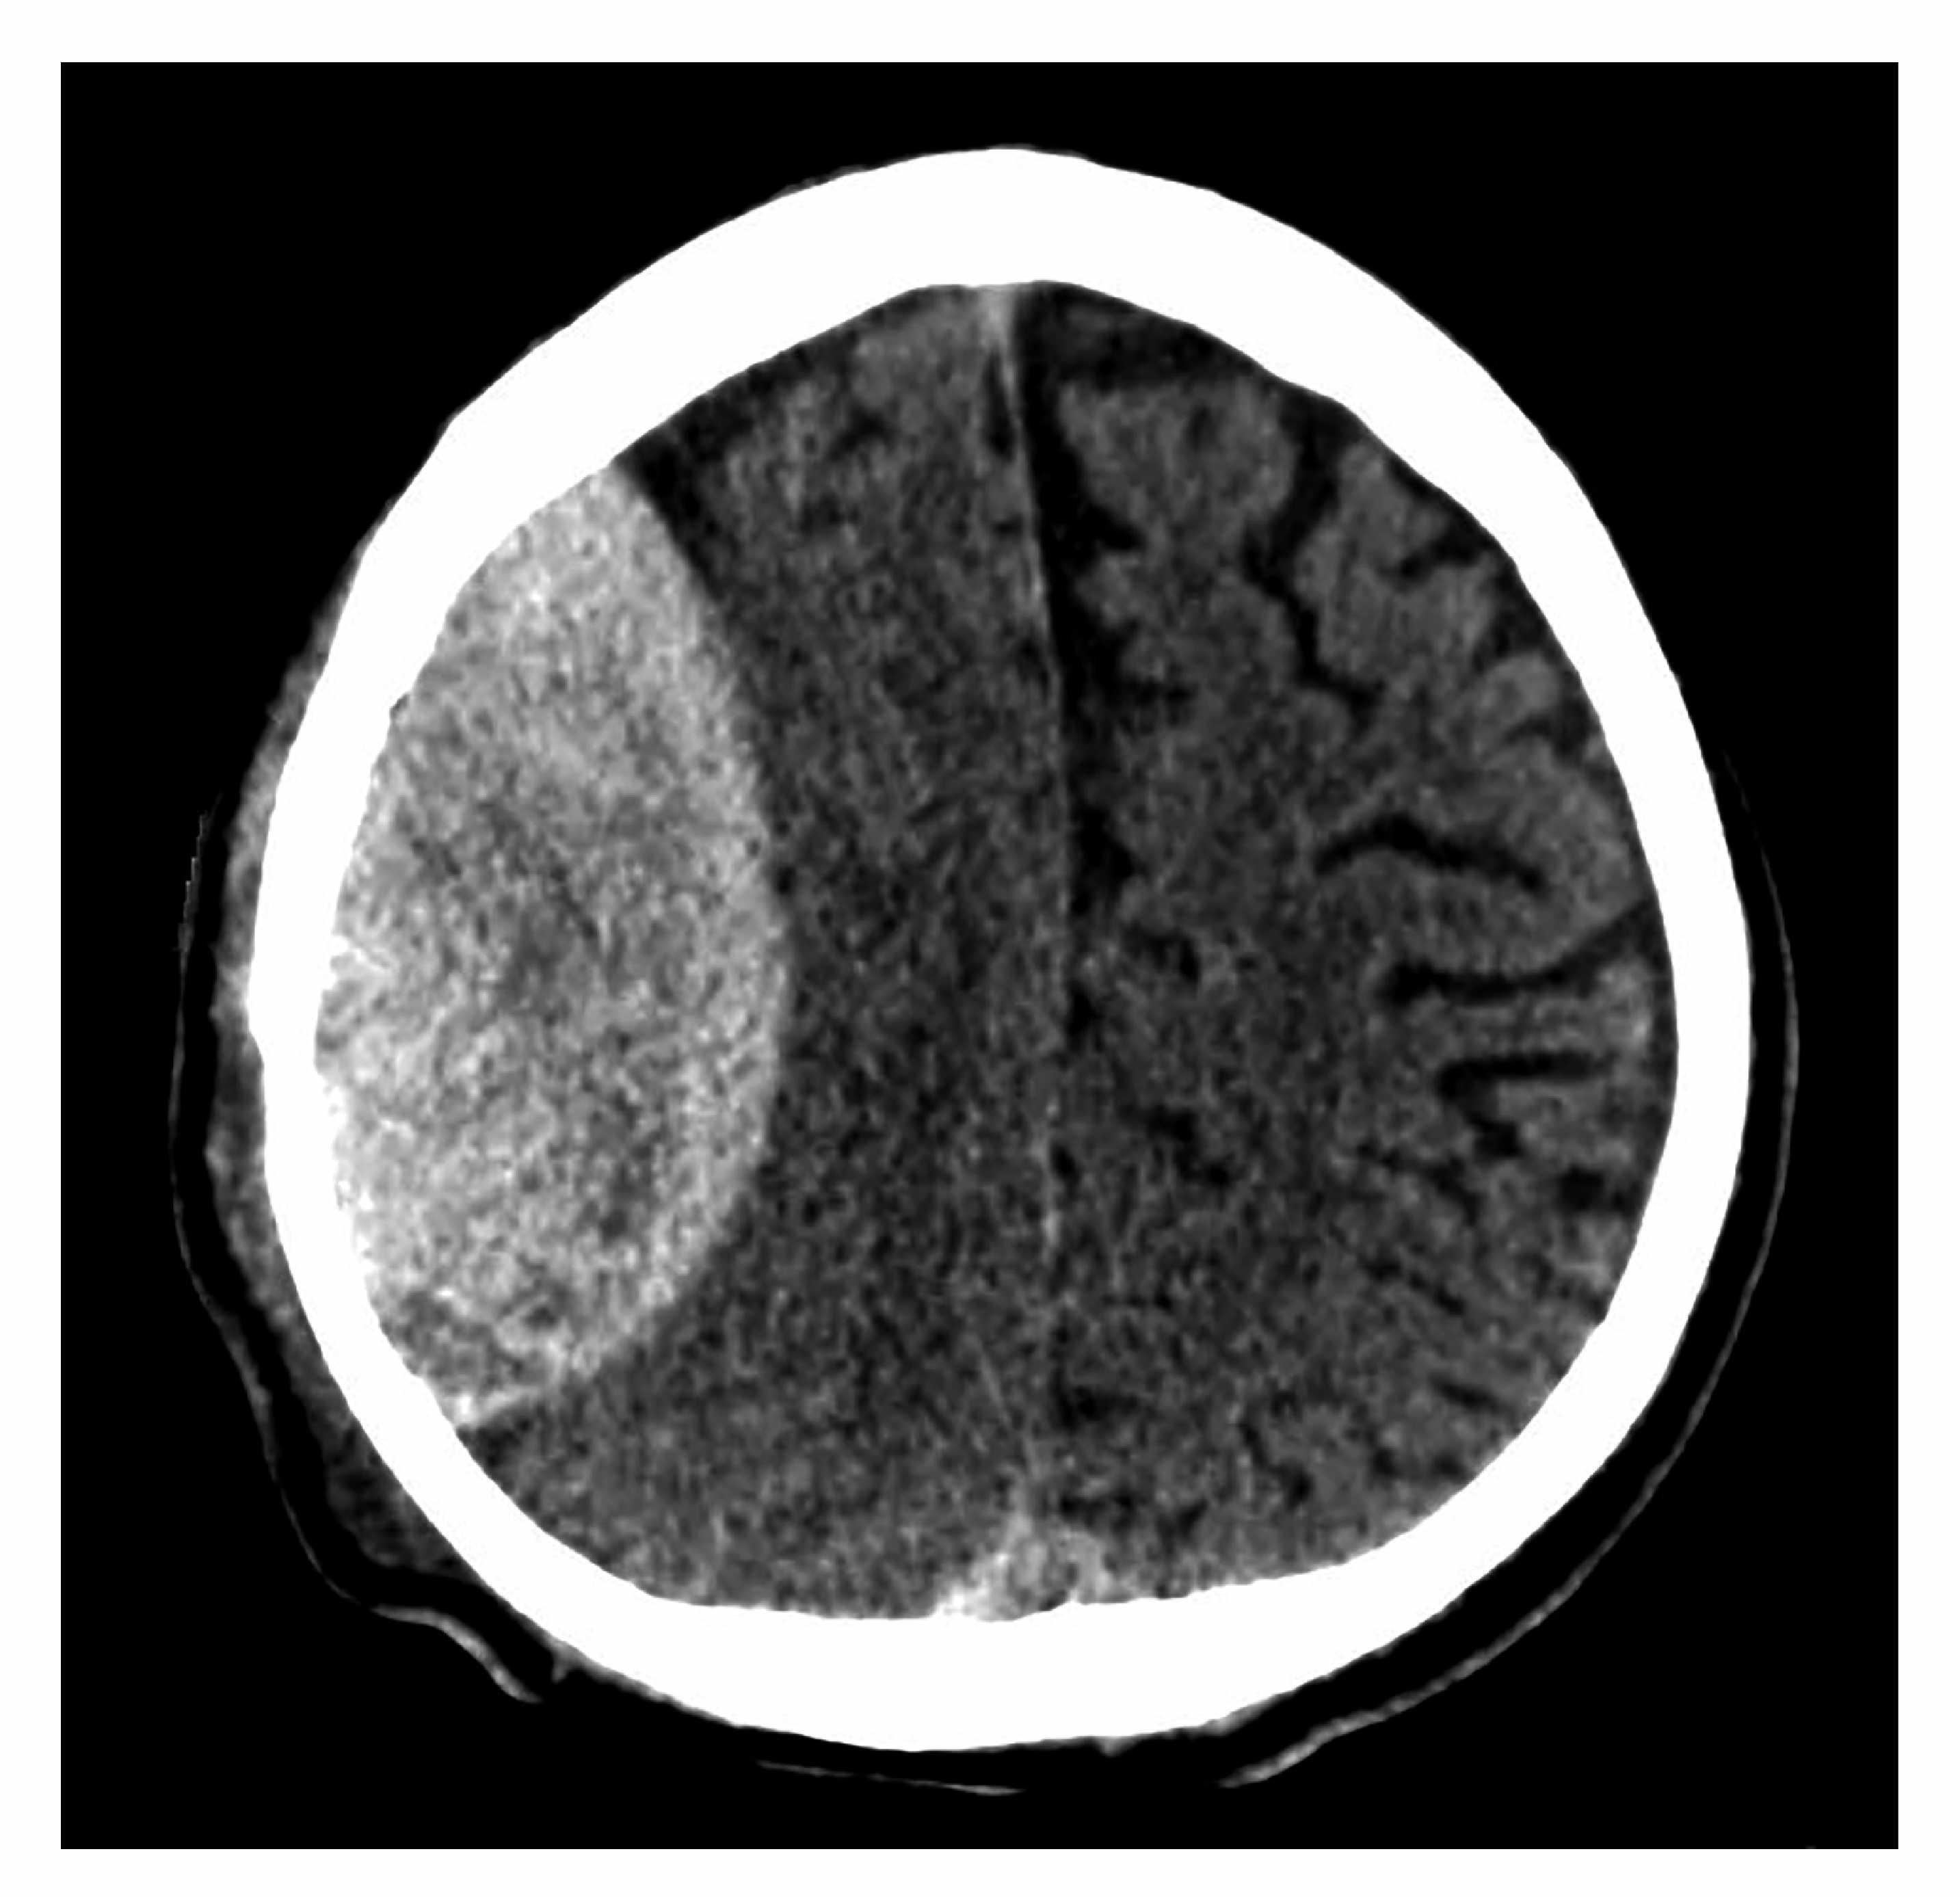

A 50-year-old skier collides with a tree. A head CT is shown above. What is the structure is disrupted?

Middle meningeal artery